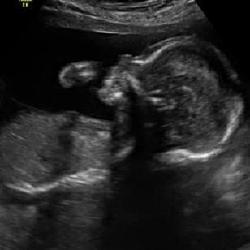

After our brother and sister-in-law had a routine ultrasound it was found that their beautiful little boy, Isaac William has a congenital heart defect. A stenosis (narrowing) of his aortic valve; which can/will lead to a decrease in function of the left side of his heart (the main pumping chamber). They have been on quite the rollercoaster with a trip to Boston and multiple strides and setbacks. We are running/walking this race to support them, to raise awareness and funds for CHD and most importantly, to get together to send many more prayers out for our amazing Bro and Sis, lil Isaac and sweet Teagan. We are warriors and will continue to lift them up in support and much needed prayer.